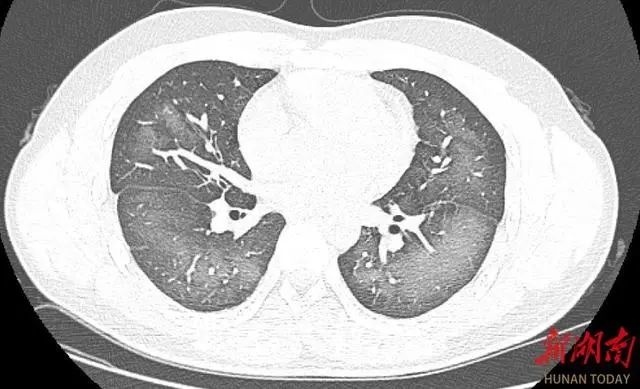

夏日炎炎 正是需要防晒的时候 市场上的防晒产品琳琅满目 其中 使用起来方便又有清凉感的 防晒喷雾 成了近几年的网红产品 不过,近日 湖南长沙一位小伙没想到 因使用防晒喷雾不当 竟给自己带来了不小的麻烦 使用防晒喷雾时误吸 20岁小伙检竟查出“白肺” 日前,20岁的长沙小伙李林(化名)在外出前使用了防晒喷雾,在对着面部喷洒时一不小心误吸,随即出现胸闷、咳嗽的症状。症状一直持续到第二天仍未好转,他急忙来到湖南省长沙市第三医院就诊。 经检查,肺部CT片显示,李林双肺赫然呈现大范围白色样病变,报告提示“白肺”。 “白肺”一般是指重症肺炎在X线或CT检查下的表现,患者肺部呈现一大片的白色状态,往往会出现呼吸困难、呼吸衰竭,严重者还会出现其他脏器功能障碍。 “白肺”常见于高龄(65岁以上)、免疫力低下、有重要器官慢性病史(如心脏病、中风史、慢性肾脏病、慢性阻塞性肺疾病等)、有多种疾病并存(比如既有高血压、糖尿病,又有心脏病、肺病、肾功能不全)等人群。